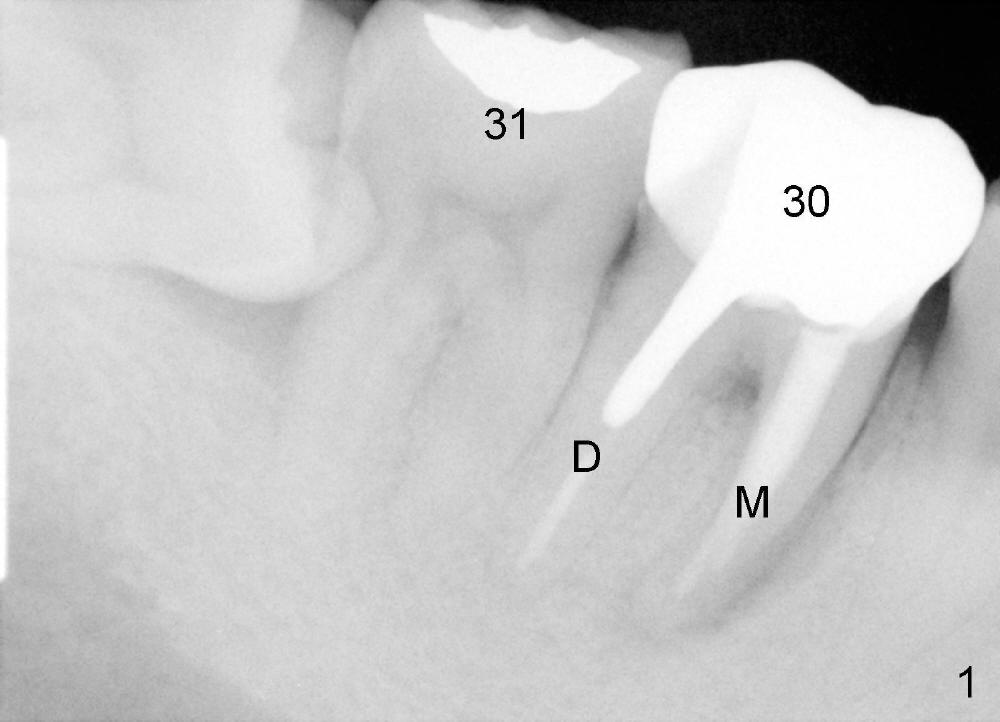

A 40-year-old man presents to clinic with chief complaint of pain in the lower right 1st molar.  Exam reveals a fistula in the mesiobuccal area.  PA shows a large radiolucency associated with the mesial root.  Where should an immediate implant be placed?